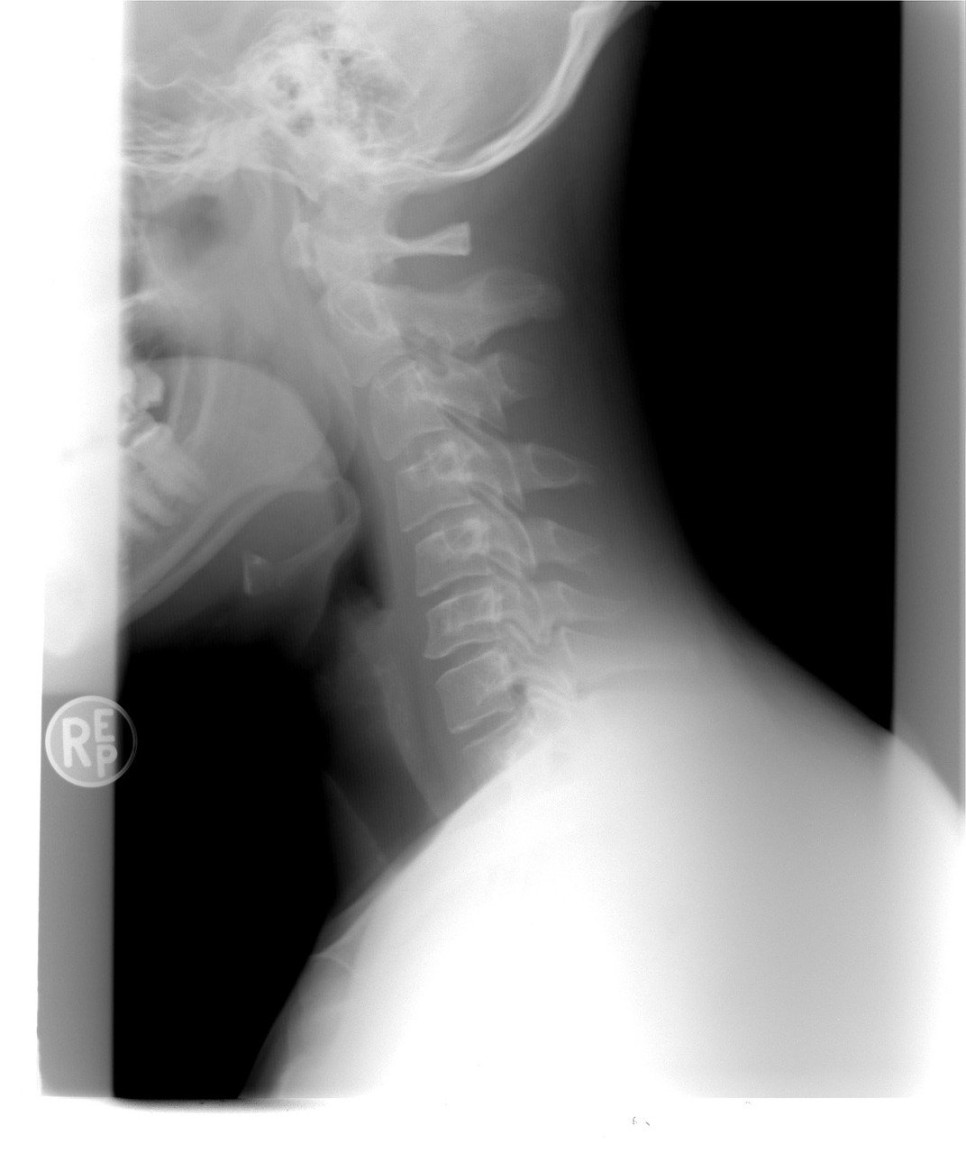

오늘은 교통사고 합의에서 분쟁 발생 위험이 있는 경추 골절의 진단을 안내하겠습니다.

교통사고 경추 골절

척추뼈 중 가장 윗부분에 해당하는 경추는 교통사고 발생 시 머리에 직접 충격이 가해진 경우에 압박골절 형태로 골절이 발생합니다.

압박 골절은 단어 그대로 강한 외력을 원인으로 뼈가 충격을 받아 압박되는 형태의 골절을 말합니다.